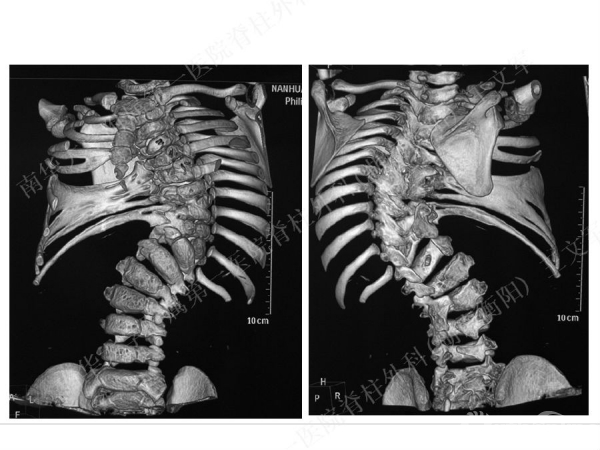

拥有完全自主知识产权的滑槽钉生长棒非融合技术,由南华大学附属第一医院脊柱外科王文军教授研发。

该技术在提供良好矫形固定效果的同时,保留了脊柱生长潜能、尽可能减少对患儿脊柱生长的影响,初步临床效果显示该系统是简单安全有效的,是严重儿童早发脊柱侧弯矫形治疗的一种有益尝试。

擅长脊柱脊髓疾病的微创及非融合手术治疗,目前率领科室开展的先进微创手术有:椎间孔镜技术、经皮穿刺腰椎外固定支架术治疗胸腰椎骨折、腹腔镜下人工腰椎间盘置换术、胸腔镜下胸椎前路手术、腰骶椎轴向融合术。率先在全国业界提出组合微创技术的理念,大大提升了脊柱微创技术的应用范围和治疗效果。拥有自主知识产权的生长棒技术在早发性脊柱侧弯术中的应用解决了儿童脊柱侧弯既早期矫形,又不影响生长发育的世界性难题。